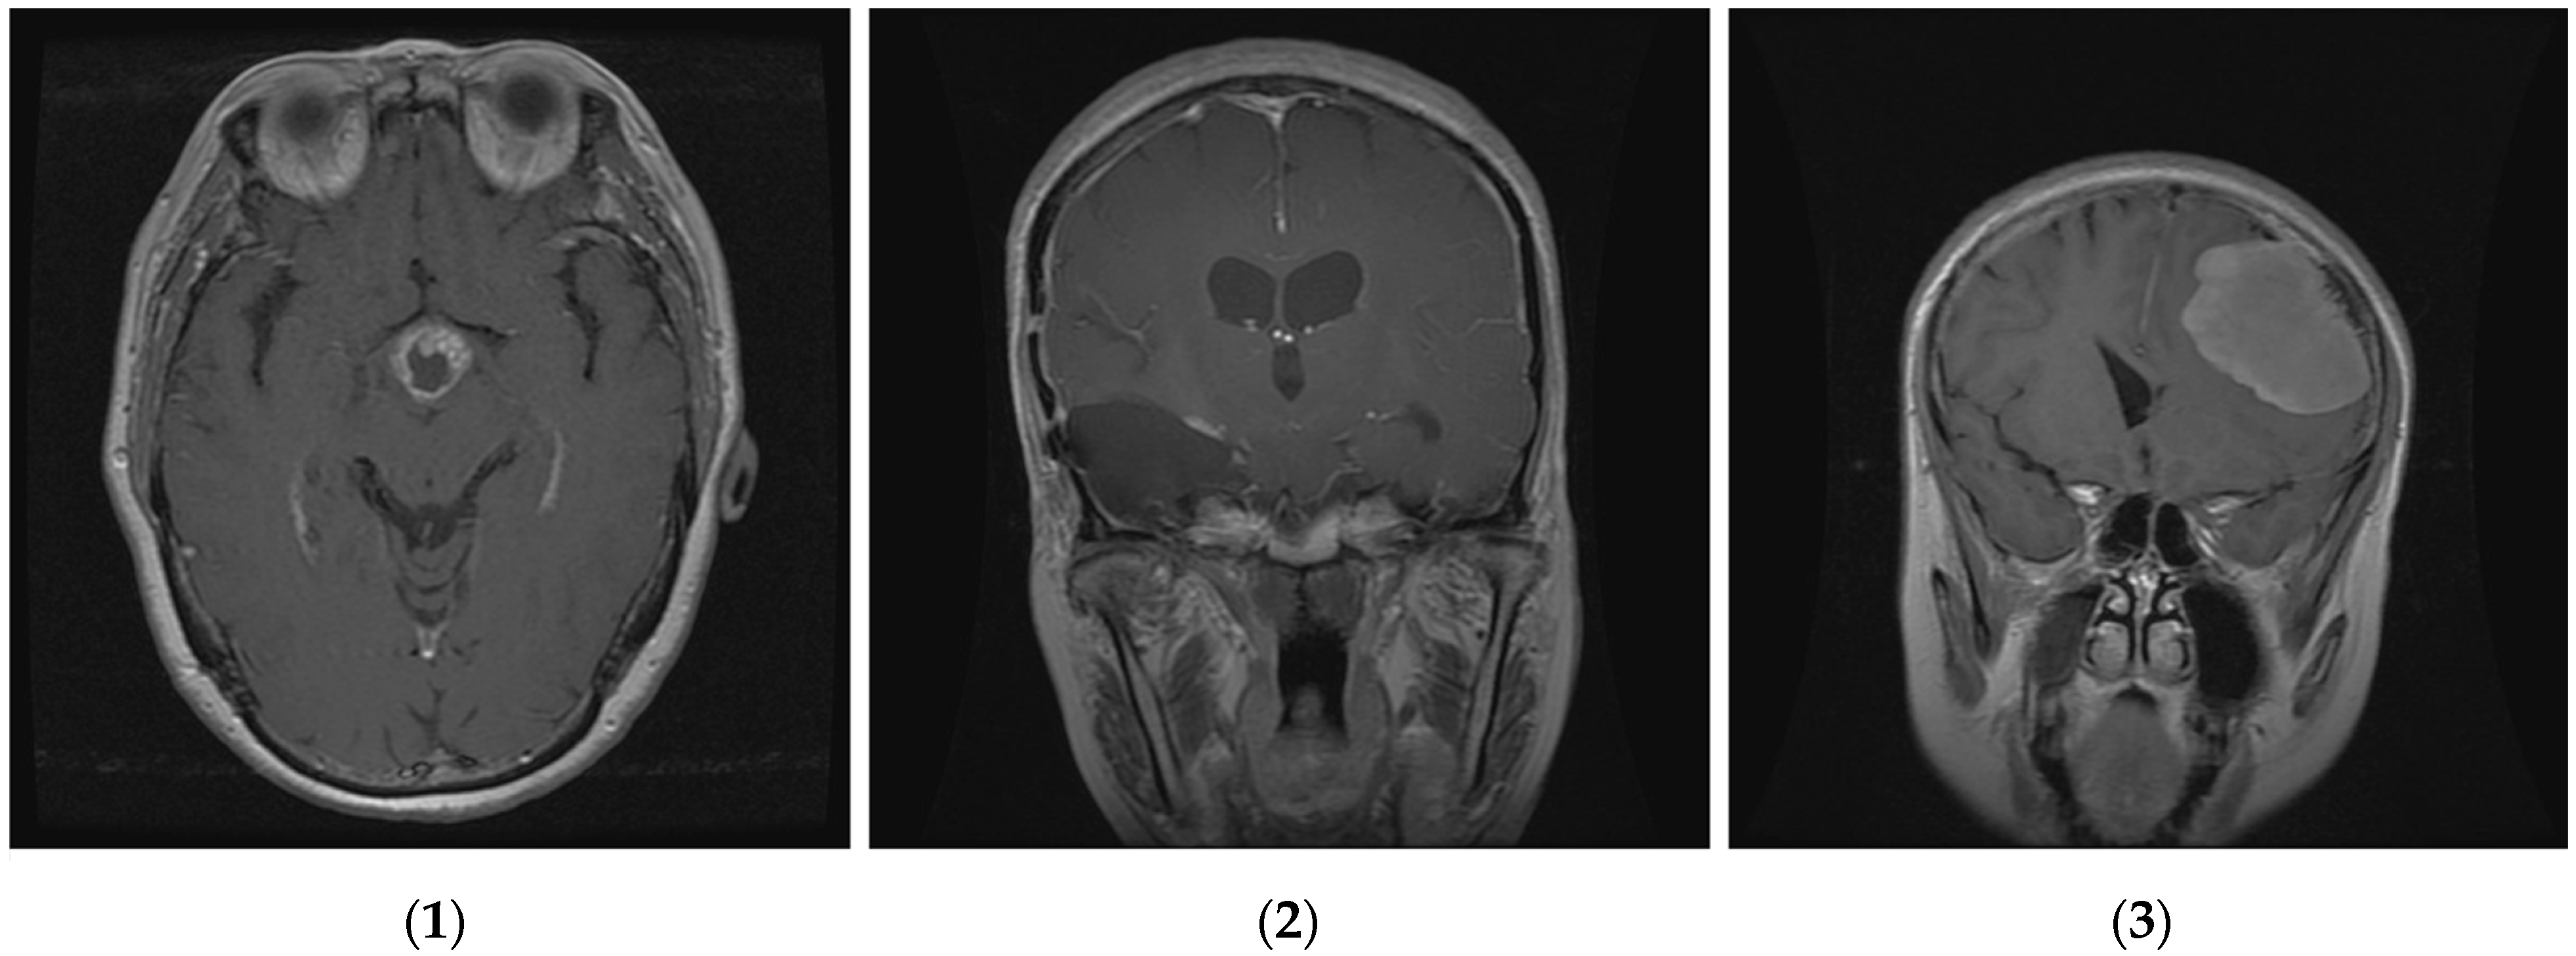

Figure 4.

Three classes of brain tumor datasets; (1) meningioma, (2) glioma, and (3) pituitary brain tumors.

The proposed method was examined and tested by using data on brain tumors gathered between 2005 and 2010 from Tianjin Medical University General Hospital and Nanfang Hospital in Guangzhou, Guangdong, China [59]. Three distinct types of brain tumors are represented in this brain tumor dataset, which consists of 3064 T1-weighted contrast-enhanced pictures from 233 patients: meningioma (708 slices), glioma (1426 slices), and pituitary tumor (930 slices). We randomly divided these images into two groups, using 80% for training and validation and 20% for testing the model. This means that the pituitary sample is divided into 744 slices to train the model and 186 slices for the test; the glioma sample is divided into 1141 slices for training and the remaining (285 slices) are used for the test; and the meningioma is divided into 566 slices for training the model and 142 slices for testing. The results are represented in Figure 3. The images are 512 × 512 pixels in size and are available as .png files. Figure 4 presents sample images from the brain tumor dataset, showcasing examples from each of the three tumor classes.